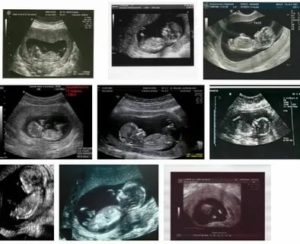

- 7 недель – головка эмбриона;

- 8 недель – конечности плода;

- 9-11 недель – косточки конечностей и точки окостенения;

- 11-14 недель – наличие или отсутствие желудка, почек, мочевого пузыря, всех пальцев плода.